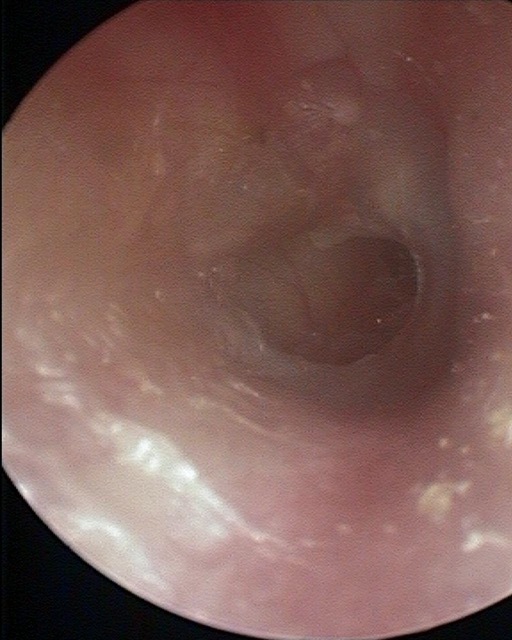

Perforation